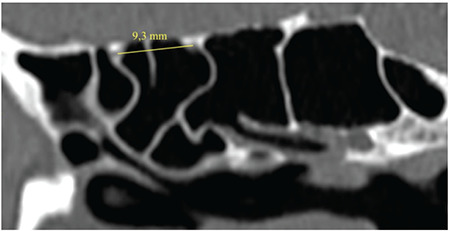

Results: There were 100 patients in this study, of whom 51% (51/100) were female and 49% (49/100) were male. Patient ages ranged from 20 to 84 years. Their average age was 40.92±14.65 years. The distance on CT scan between the posterior and anterior ethmoidal arteries was 13.98±1.95 mm (9.3 to 18.6 mm). This distance in males was significantly higher than female (p=0.001). However, there is no difference in this distance between the left and right side (p=0.67). The distance between the posterior ethmoid artery and skull base ranged from 0 to 5.4 mm. The average distance between the posterior ethmoidal artery and skull base on CT scan was 0.95±0.94 mm. The diameter of the posterior ethmoid artery was 0.57-0.91 mm. The average diameter of the posterior ethmoidal artery on CT scan was 0.76±0.09 mm.